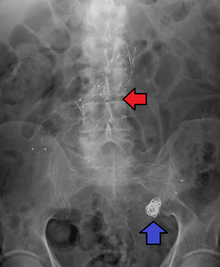

Fusiform aneurysms ("spindle-shaped" aneurysms) are variable in both their diameter and length; their diameters can extend up to 20 cm (8 in). They often involve large portions of the ascending and transverse aortic arch, the abdominal aorta, or less frequently the iliac arteries.[3]:357

- The aorta, namely aortic aneurysms including thoracic aortic aneurysms and abdominal aortic aneurysms.

Aortic and peripheral aneurysms

For aneurysms in the aorta, arms, legs, or head, the weakened section of the vessel may be replaced by a bypass graft that is sutured at the vascular stumps. Instead of sewing, the graft tube ends, made rigid and expandable by nitinol wireframe, can be easily inserted in its reduced diameter into the vascular stumps and then expanded up to the most appropriate diameter and permanently fixed there by external ligature.[24][25] New devices were recently developed to substitute the external ligature by expandable ring allowing use in acute ascending aorta dissection, providing airtight (i.e. not dependent on the coagulation integrity), easy and quick anastomosis extended to the arch concavity[26][27][28] Less invasive endovascular techniques allow covered metallic stent grafts to be inserted through the arteries of the leg and deployed across the aneurysm.